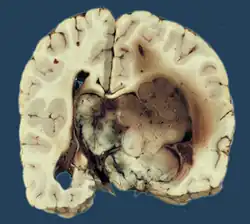

Choroid plexus papilloma, also known as papilloma of the choroid plexus, is a rare benign neuroepithelial intraventricular WHO grade I lesion found in the choroid plexus.[1] It leads to increased cerebrospinal fluid production, thus causing increased intracranial pressure and hydrocephalus.[2]

Choroid plexus papilloma occurs in the lateral ventricles of children and in the fourth ventricle of adults. This is unlike most other pediatric tumors and adult tumors, in which the locations of the tumors is reversed. In children, brain tumors are usually found in the infratentorial region and in adults, brain tumors are usually found in the supratentorial space. The relationship is reversed for choroid plexus papillomas.

CPPs are rare tumors of neuroectodermal origin. They make up 0.4 to 0.6 percent of all intracranial neoplasms in children and are the third most prevalent congenital brain tumors after teratomas and gliomas.[3] With a median age upon diagnosis of 3.5 years, this lesion is often a disease of infancy. They often reside supratentorial in the lateral ventricles of infants (most commonly in the atrium).[4] The fourth ventricle in adults is the optimum location.[5] Adults rarely have it at the cerebellopontine angle.[4]

Choroid plexus tumors are divided into three categories by the World Health Organization (2016):[9] papillomas (grade I), atypical tumors (grade II), and carcinomas (grade III). Less than two mitotic figures per 10 high power fields are present in CPPs, two to five are present in atypical ones, and more than five are present in carcinomas. The tumors are visible as pink, soft, spherical lumps with erratic projections and considerable vascularity.